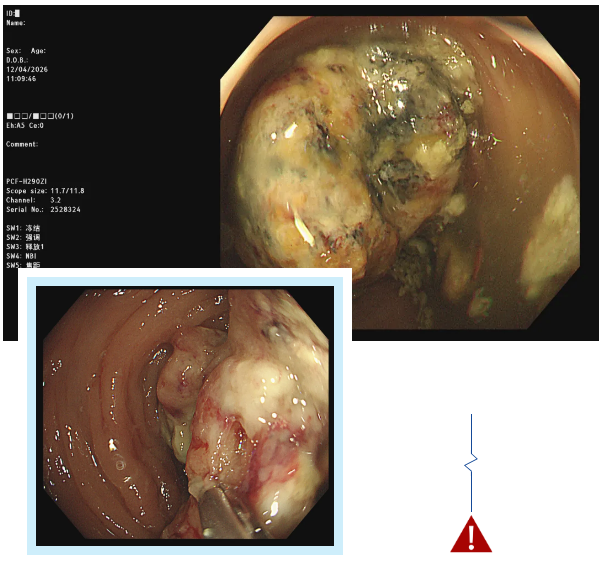

经无痛肠镜检查,吕主任发现李阿姨脾区肠壁增厚,肠道已经出现狭窄,肠镜无法顺利通过。随后取肿物进行活检,最终确诊为结肠癌。这个结果给李阿姨和她的家人敲响了警钟,也让我们深刻意识到,肠道发出的一些看似不起眼的信号,可能隐藏着致命的危机。

肠镜插入与观察:待患者进入睡眠状态后,医生会将带有摄像头的肠镜从肛门缓缓插入肠道,通过肠道蠕动逐步推进。在插入过程中,医生会不断注入少量空气,使肠道扩张,以便清晰地观察肠道黏膜的情况。肠镜上的摄像头会将肠道内部的画面实时传输到显示器上,医生可以仔细查看肠道内是否有息肉、炎症、溃疡、肿瘤等病变。如果发现可疑病变,医生还可以通过肠镜上的活检通道取少量组织进行病理检查,以明确病变的性质。